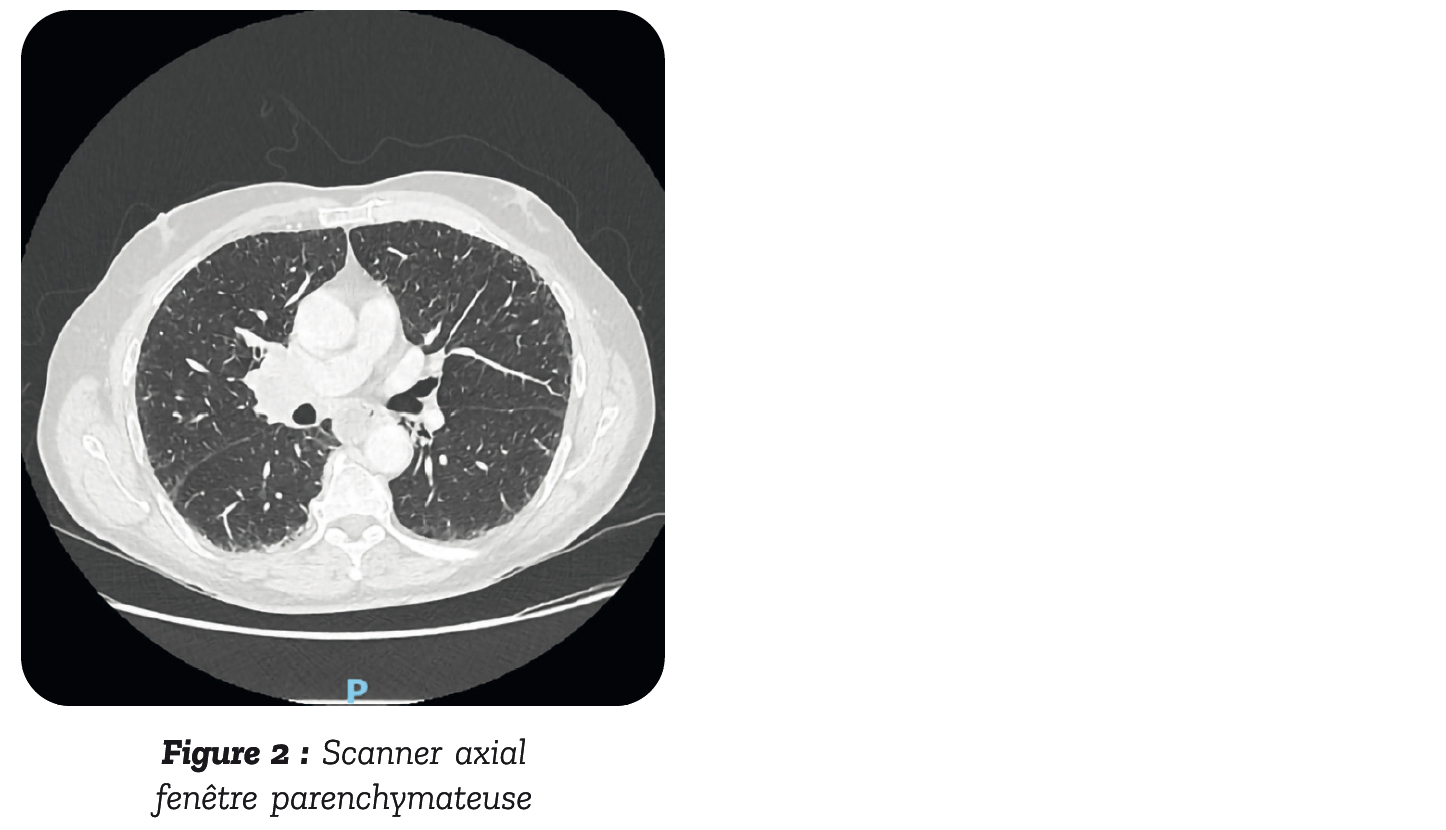

Dans le cadre des symptômes neurologiques, un scanner thoraco- abdomino-pelvien injecté est réalisé et ne montre pas de compression médullaire. En revanche, il met en évidence une masse médiastin hilaire droite de 42 x 32 mm (figure 1 et 2), avec dilatation œsophagienne.

Il a ensuite été transféré en pneumologie pour l'exploration de la masse pulmonaire où une fibroscopie bronchique avec biopsie Trans trachéale a permis d'identifier un carcinome bronchique à petites cellules. Dans le cadre du bilan d'extension, un TEP-TDM a été réalisé qui retrouvait une hyperfixation de la masse pulmonaire à droite, sans autre site d'hy- permétabolisme et l'IRM cérébrale ne retrouvait pas de lésion secondaire.